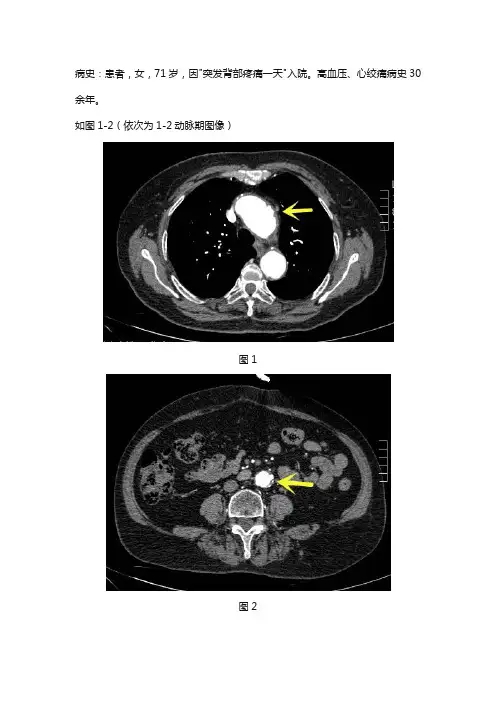

病史:患者,女,71岁,因"突发背部疼痛一天"入院。

高血压、心绞痛病史30余年。

如图1-2(依次为1-2动脉期图像)图1图2基础解剖影像:图3图4图5图6图3-6所示为正常中年人主动脉增强图像。

影像诊断:如图1-2所示。

影像描述:主动脉弓与腹主动脉管壁厚度不均,可见低密度充盈缺损影,增强局部可见宽基底龛影向外突出,未突破外膜。